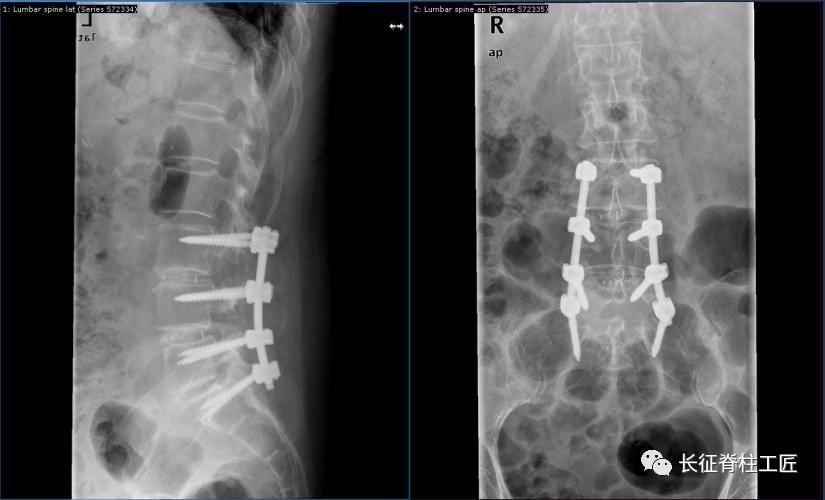

脊柱外科史国栋主任带领团队详细讨论,决定行椎管减压植骨融合内固定术。秉持微创的理念,术中通过精确的切口设计、肌肉组织的保护、手术时间的控制、后侧韧带复合体的保留等措施,在开放的手术中微创的完成了手术。

腰椎管狭窄手术核心是椎管及神经根的减压,减压术后要进行脊柱稳定性重建,以防止术后脊柱失稳的发生,椎管减压植骨融合内固定术应用于复杂型的腰椎管狭窄患者。微创的理念下开放手术具有以下优势:

手术时间的减少对患者的益处是显而易见的,临床来看,单节段狭窄患者平均手术时间为1小时,两个节段减压融合内固定1.5小时,三个节段一般2小时。手术时间越短,出血量越少,术后感染等并发症越低。